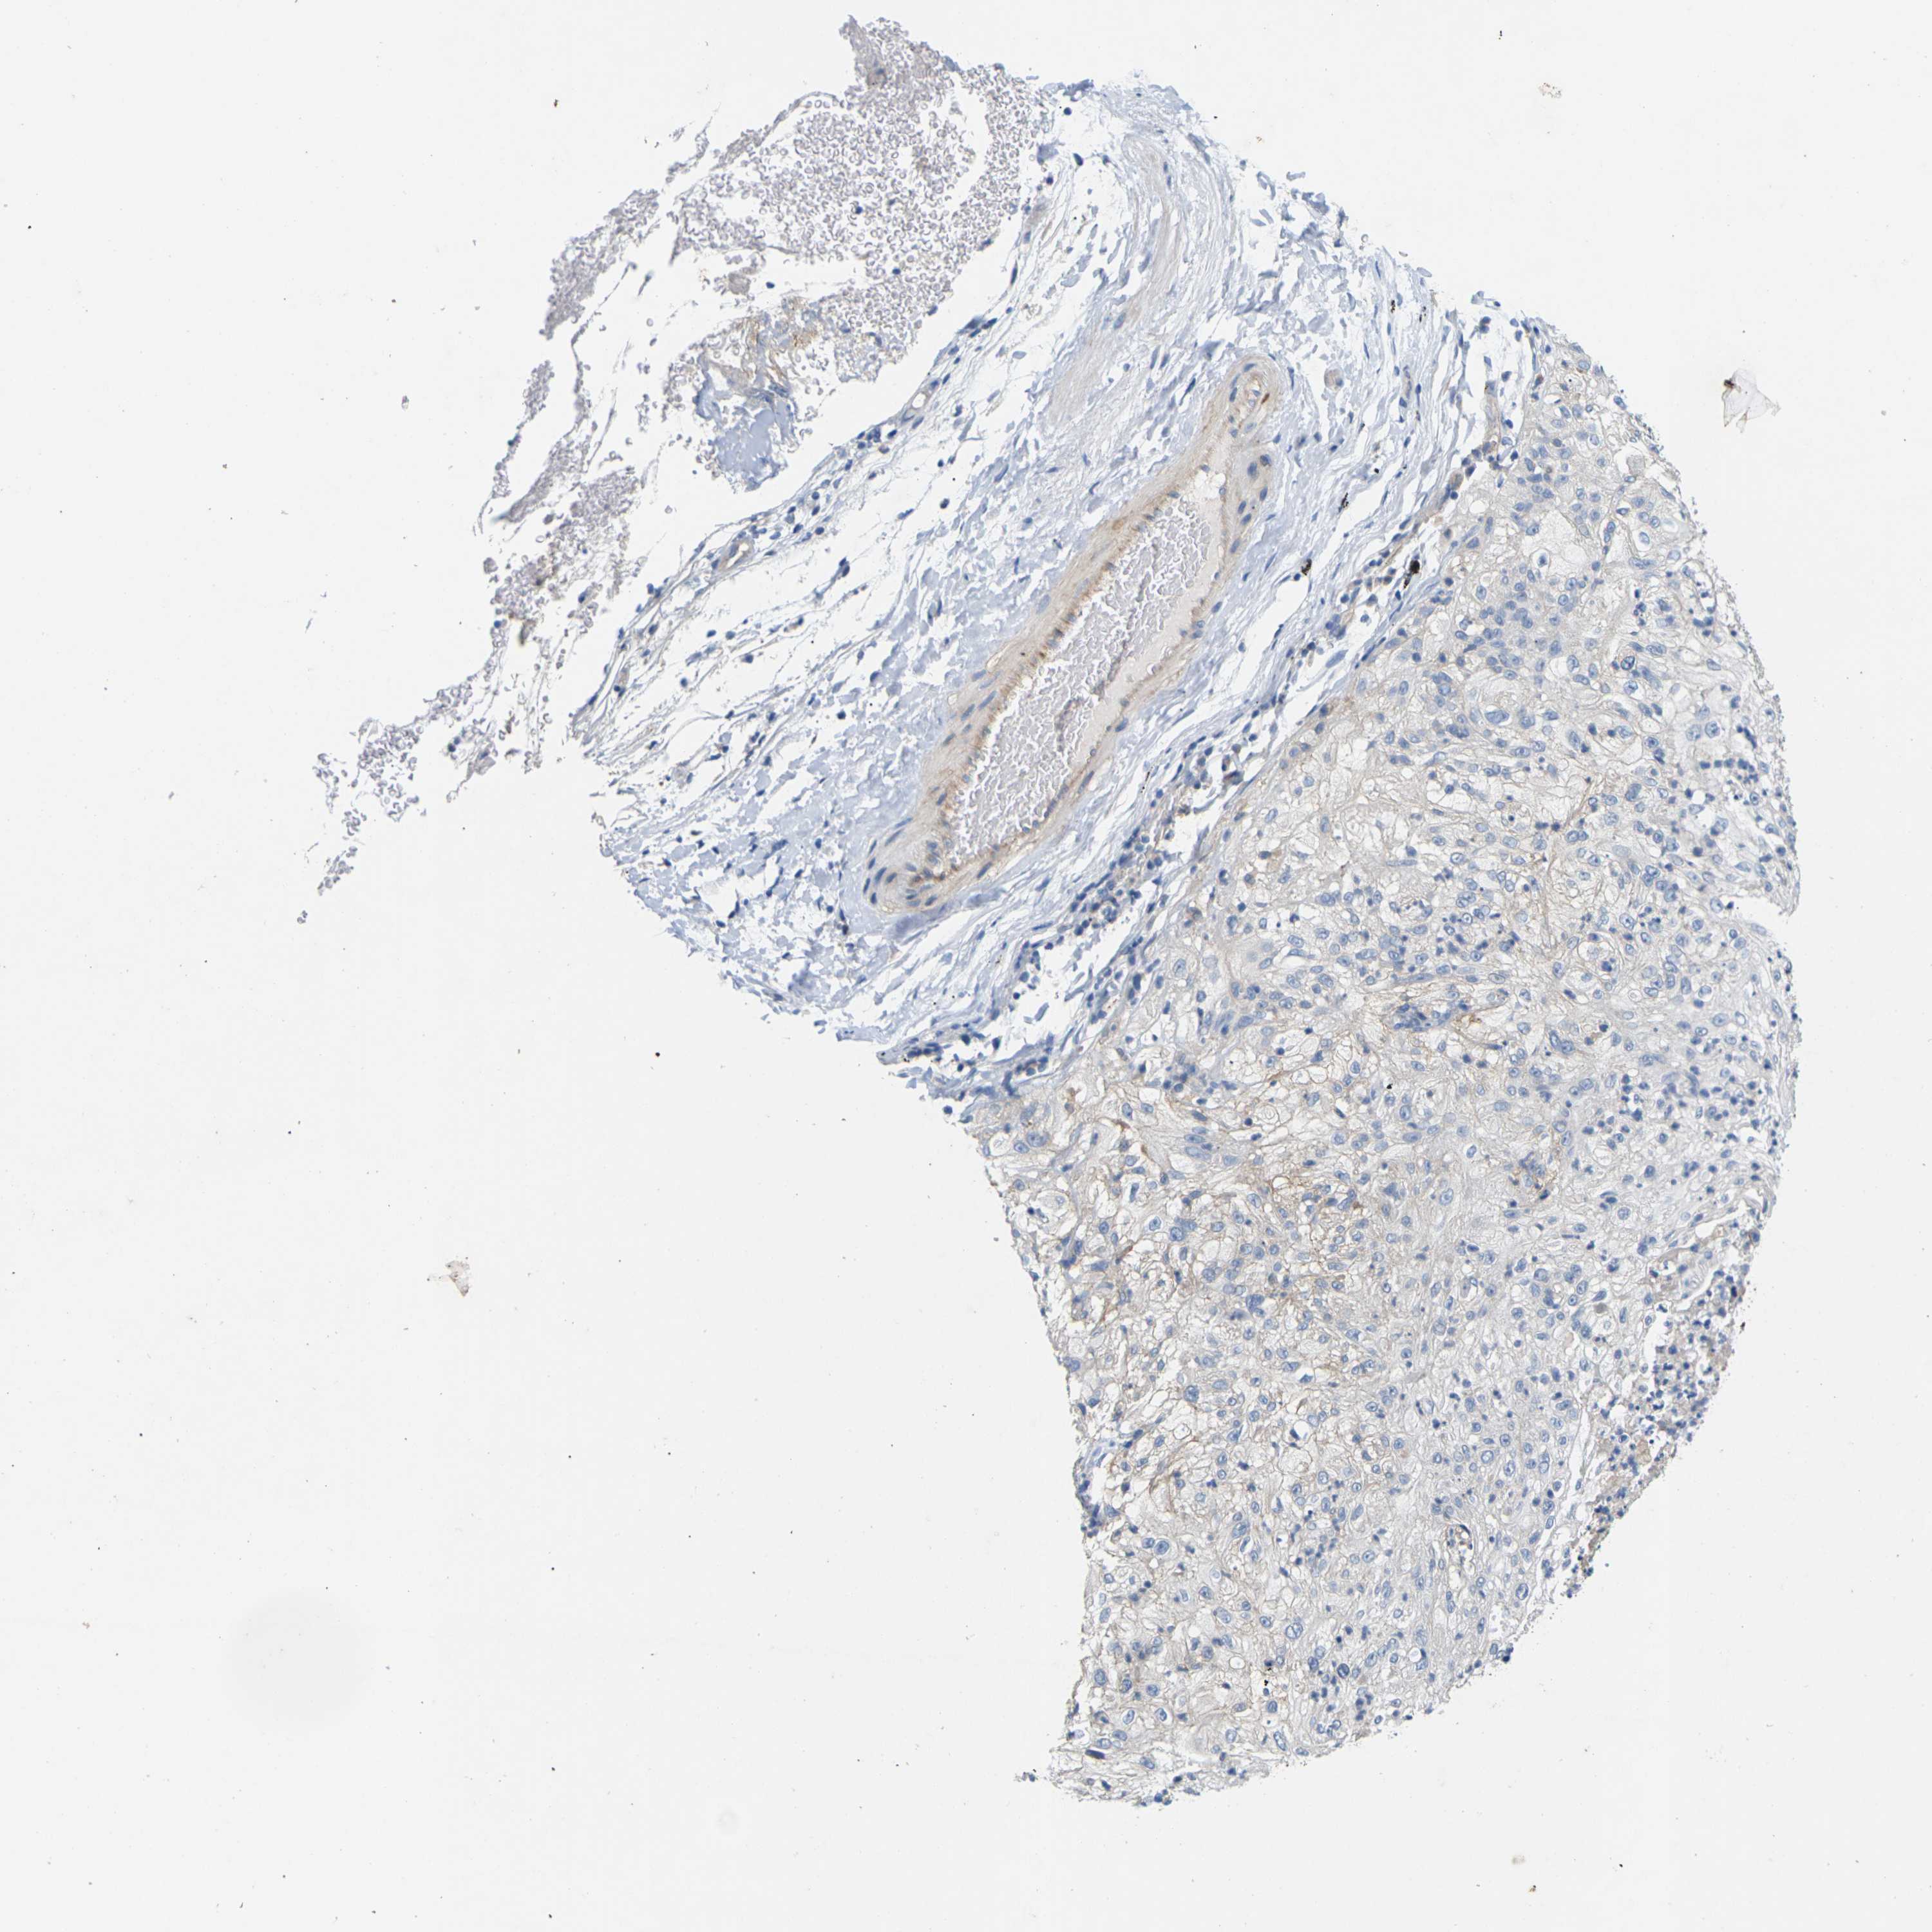

ITGA5 is potential prognostic, high expression is unfavorable in Lung Adenocarcinoma (validation)

Best expression cut offi

When clicking on this number, the vertical dashed line indicating cut-off, the interactive survival plot, and the Kaplan-Meier curve will be adjusted to show results based on the best expression cut-off.

: 40.8